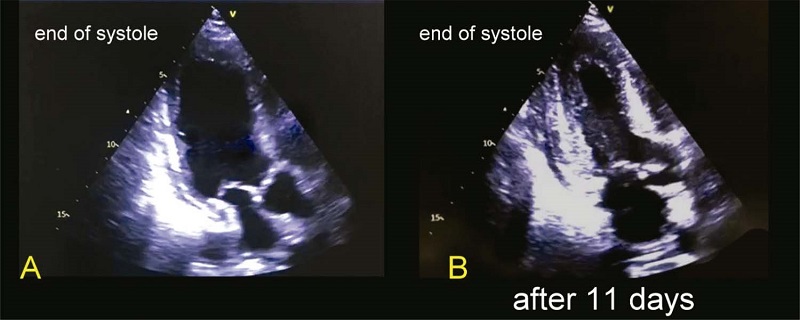

A low occurrence of left and right ventricular systolic dysfunction was observed, and 35.0% of the population had a normal diastolic function. In the subgroup analysis, we found a lower proportion of normal left ventricular systolic function, normal diastolic function, and left atrial enlargement in patients with elevated troponin (above the 99th percentile). There was also a lower prevalence of diastolic dysfunction among hypertensive and diabetic patients, and a higher prevalence of left atrial enlargement in hypertensive patients. Furthermore, we found three cases of Takotsubo cardiomyopathy that showed complete recovery after 10 days ( Figure 3).

A: admission echocardiogram; B: echocardiogram on day 11 from admission.